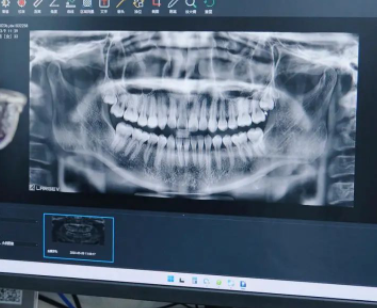

虽然3D口扫已经很厉害了,但这里的口腔检查项目还包括了口腔全景影像和正侧面CT三项。医生还要根据这些进一步分析你的口腔结构,还顺便提醒了小伙伴的智齿该拔了。